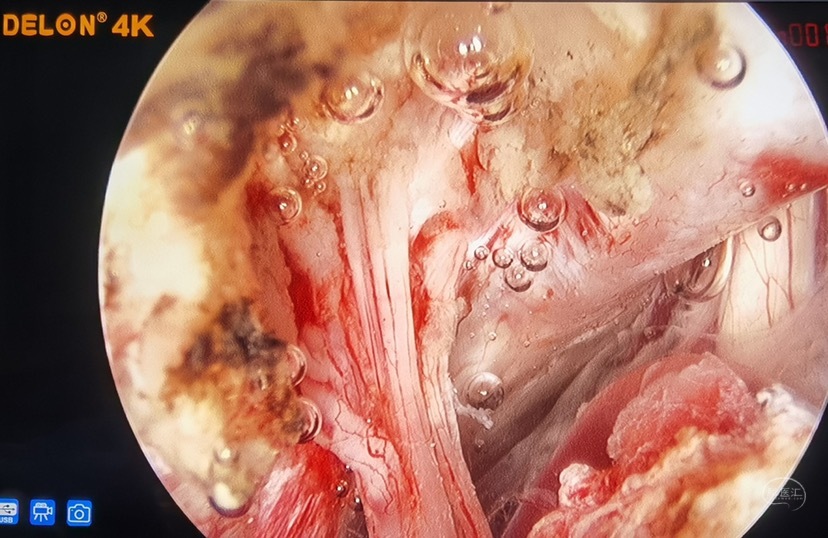

专家简介

朱伟杰,解放军第960医院(原济南军区总医院)神经外科主任,医学博士。山东省医学会神经外科分会副主任委员,山东省优秀医师,第42届中日笹川奖学金高级研究学者。参加首批联合国赴苏丹国际维和部队,在战地医院主刀为外军士兵成功实施开颅手术,获联合国个人突出贡献奖。擅长颅脑和脊髓疾病的微创治疗和神经外科疑难、复杂病变的外科治疗。